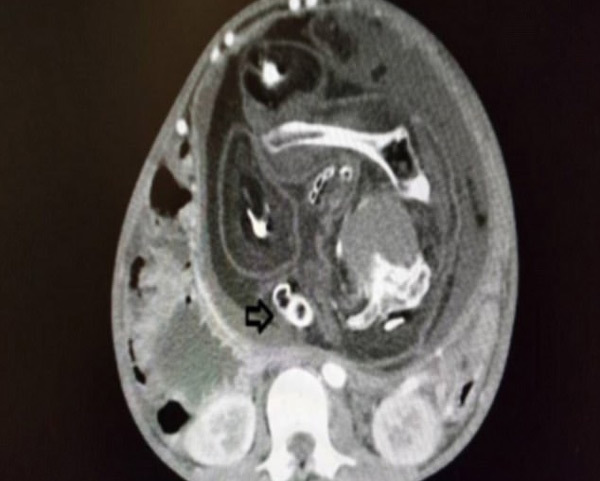

Hình ảnh phôi thai người em song sinh trong bụng cậu bé 15 tuổi qua chụp CT. (Ảnh: BMJ Case Reports) |

Lúc đầu nghi vấn bệnh nhi có khối u, các bác sĩ tại bệnh viện Sultan Abdul Halim thuộc thành phố Sungai Petani đã yêu cầu chụp CT cắt lớp. Hình ảnh chụp cho thấy trong bụng bệnh nhi chứa một vật thể dài 23,8cm có dấu hiệu phát triển cột sống.

Các bác sĩ đã làm phẫu thuật tách bóc, bất ngờ phát hiện trong đó là một phôi thai nặng 1,6kg có tóc, bộ phận sinh dục và da bọc, song tứ chi bị biến dạng và không có miệng.